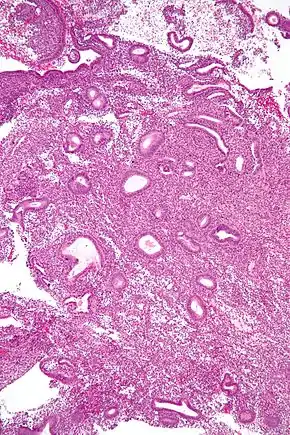

![]() Micrograph showing an endometrial biopsy with simple endometrial hyperplasia, where the gland-to-stroma ratio is preserved but the glands have an irregular shape and/or are dilated. H&E stain. | |